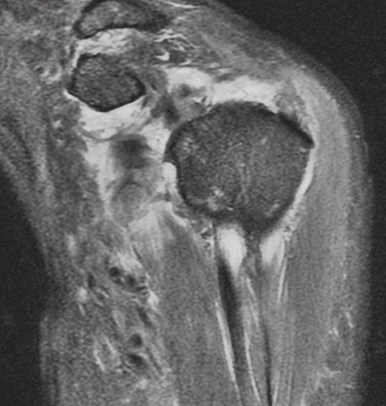

75 y/o s/p dislocation

Dislocation pathology is typically different in older patients than younger patients. The great majority of first time dislocators under the age of 40 suffer a bankart lesion (avulsion of the labral ligamentous complex on the glenoid side). Older folks often suffer a rotator cuff tear including the supraspinatus or subscapularis (or both). This patient had an SST tear but in addition also has a HAGL lesion (humeral avulsion of the glenohumeral (IGHL) ligament). She also has subscapularis partial tearing associated with a near complete dislocation of the biceps (findings that I think were preexisting). Reference article.

HAGL lesion and rotator cuff tears